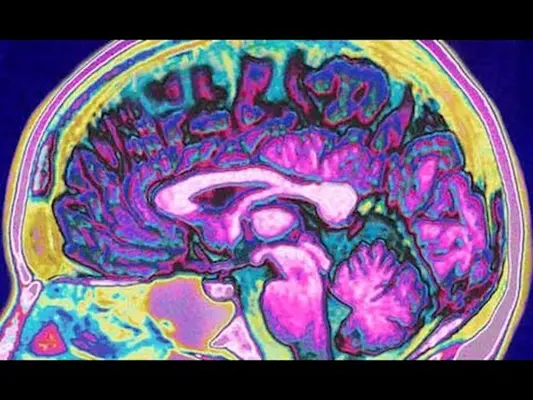

Otro grupo de participantes fue expuesto a estos olores e imágenes, así como los de los controles sanos, y se les pidió que calificaran cuánto les gustaba la gente, mientras que sus actividades cerebrales se midieron en un escáner de RM.